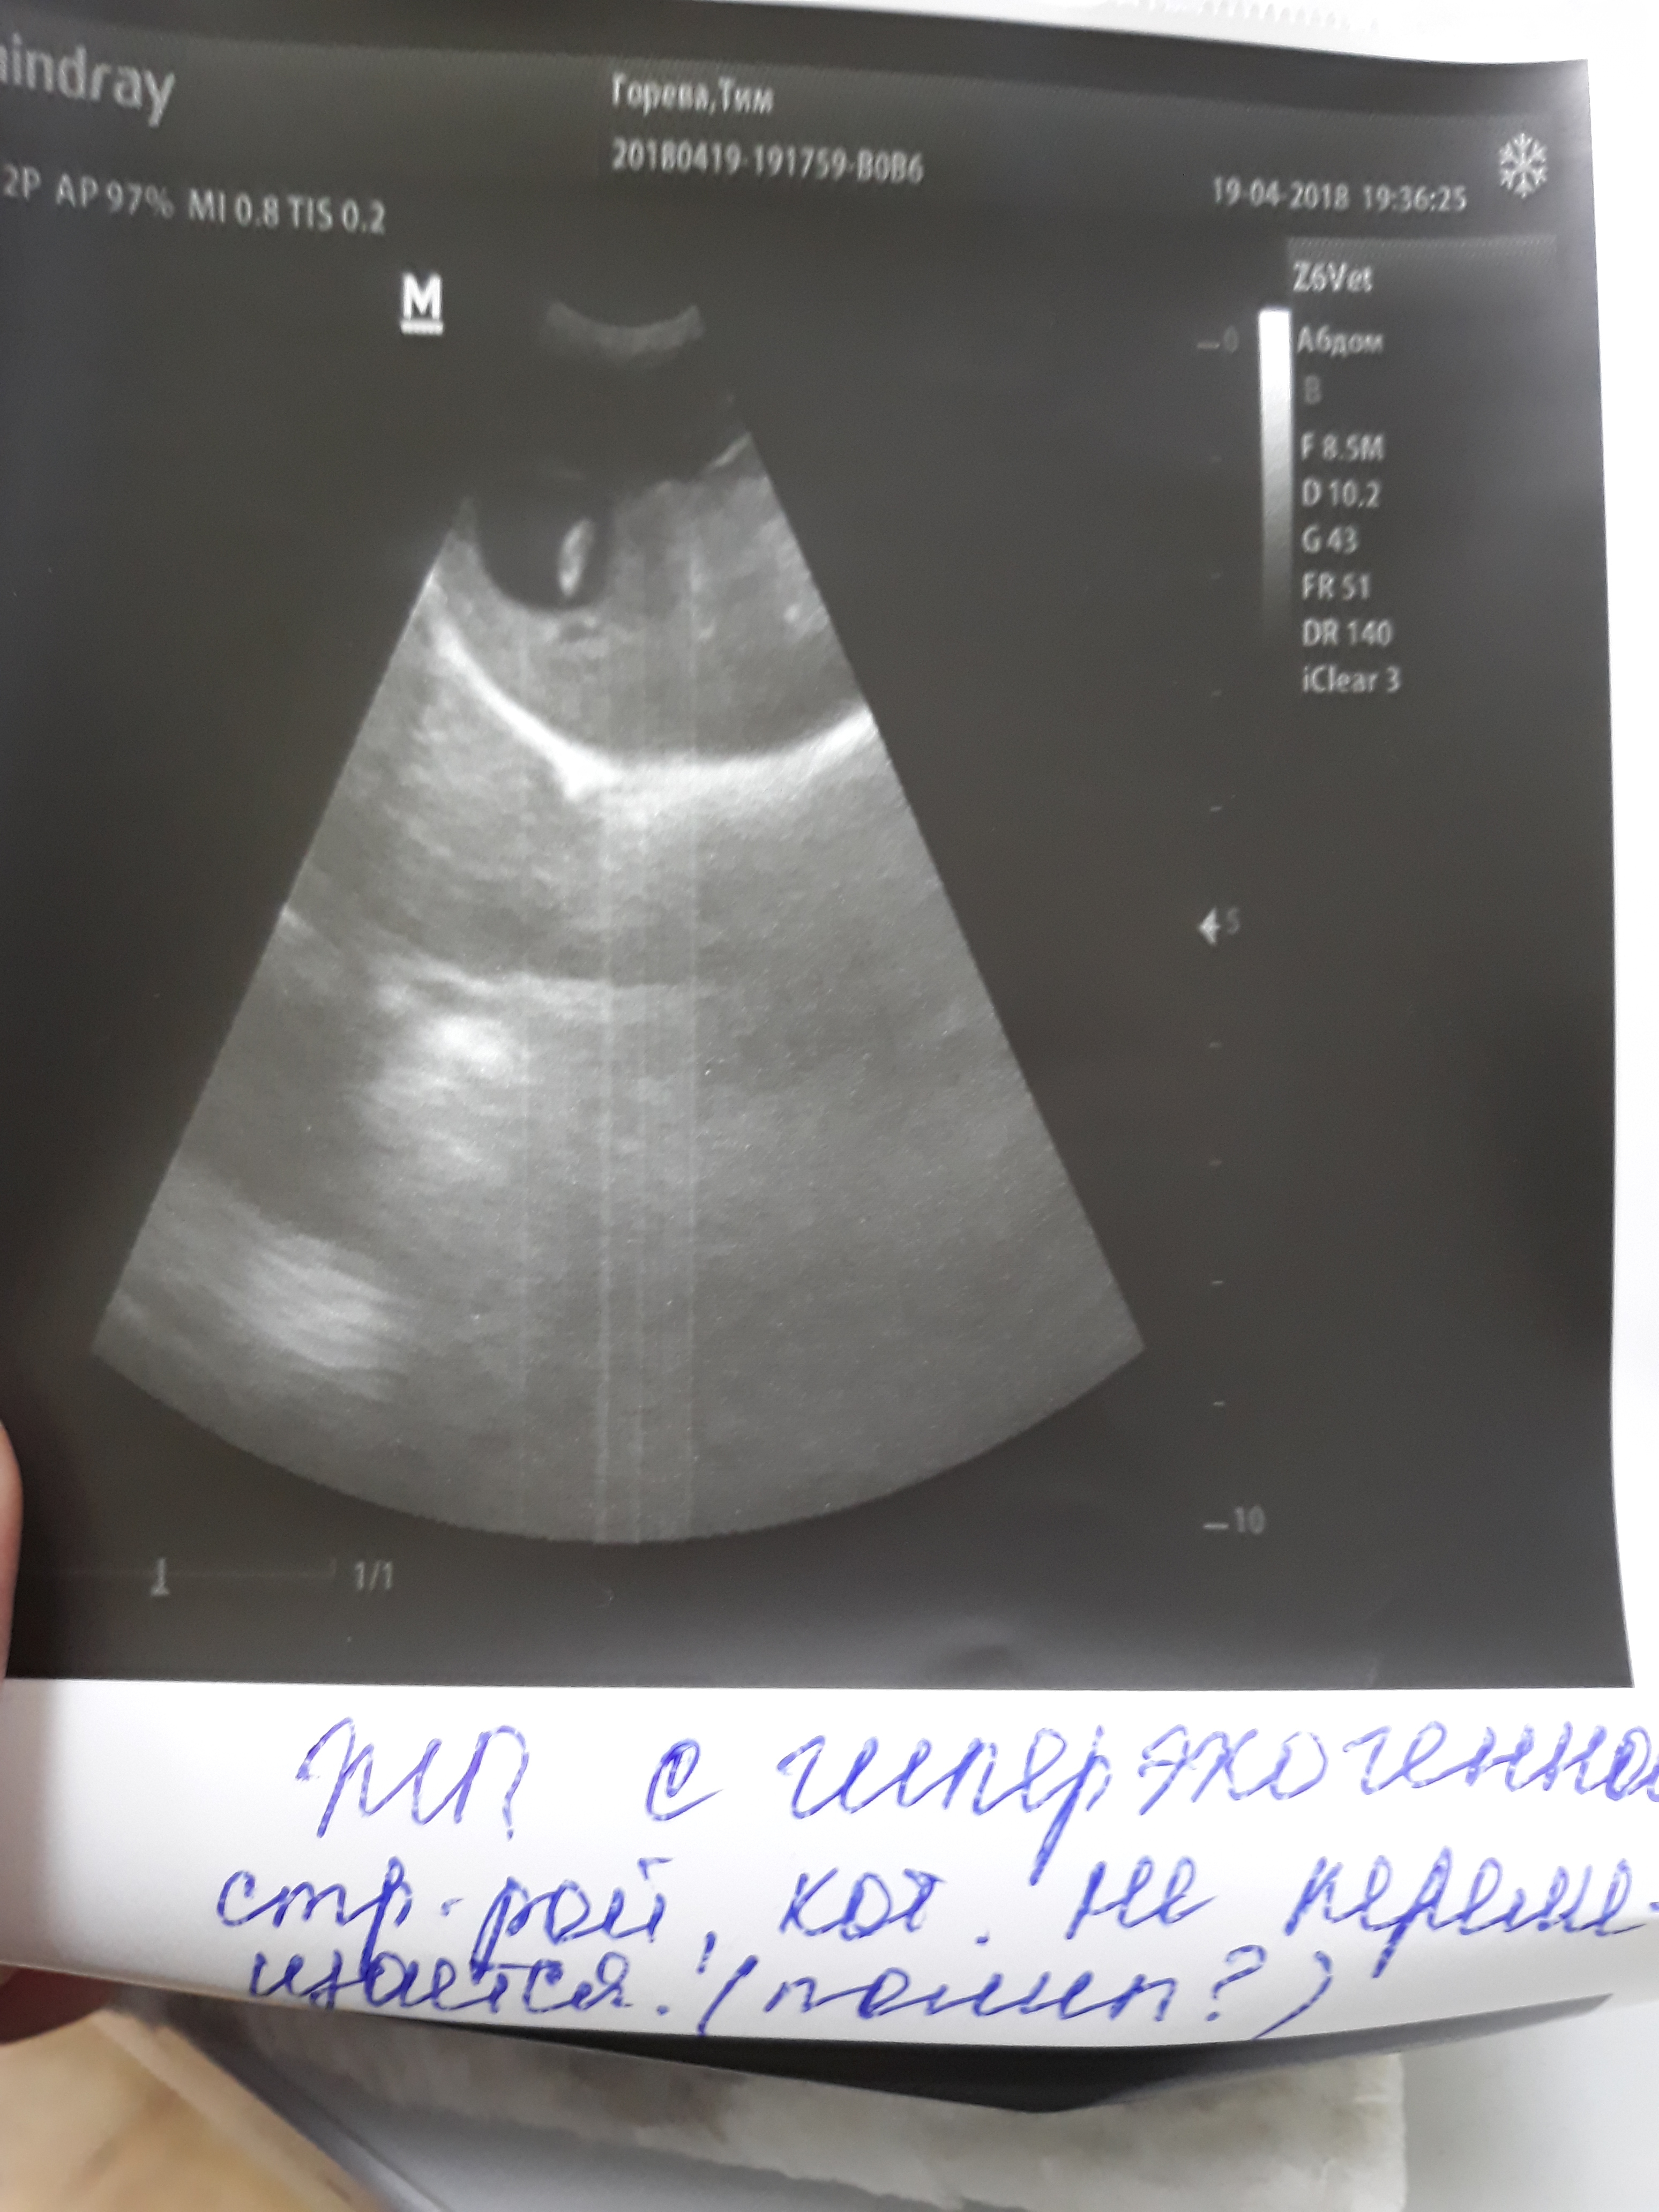

Получили мы наши анализы... Я, мягко говоря, в растерянности.. Ждала других результатов... Несмотря на видимо улучшение состояния здоровья Тимошки, анализы стали хуже

и ОАК, и добавились проблемы с печенью.. Хотя по узи печень и почки в норме, толщина стенки желудка в норме, а вот в желчном пузыре увидели что-то.. Сами не знают что. Единственное, что предполагают-полип.. Но.. Три недели назад на узи его не было...температура опять сегодня была ниже нормы.

То есть снова одни вопросы